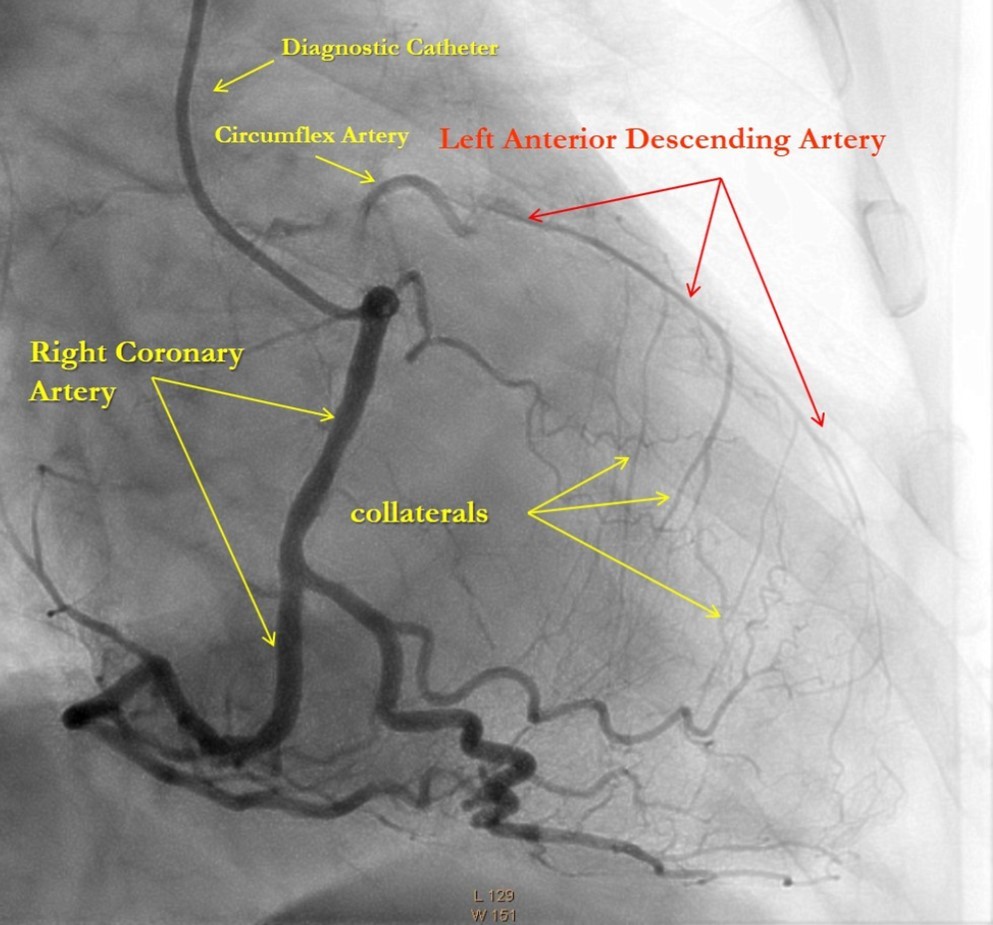

After medical treatment and comparable improvement in the patient's condition, expected risks were re-evaluated. After consulting with the patient and family members (they did not agree to the operation based on past experience) it was resolved to perform repeated CAG and to attempt revascularization of the LAD artery, (stenting). However, repeated CAG additionally revealed chronic 100% occlusion of the LMCA (Figure 1), and also CX occlusion, which was unexpected, and thereby significantly decreasing the likelihood of procedural success. In this case, the patient's heart was supplied only through the right coronary artery, which partially supplies the occluded left anterior descending and circumflex arteries through the contralateral collateral blood flow (Figure 2). Acute LMCA occlusion in most of the cases is fatal and survival is possible only in patients with a dominant RCA providing sufficient collateral formation.

Figure 2.Right Coronary Artery with developed right-to-left collaterals.